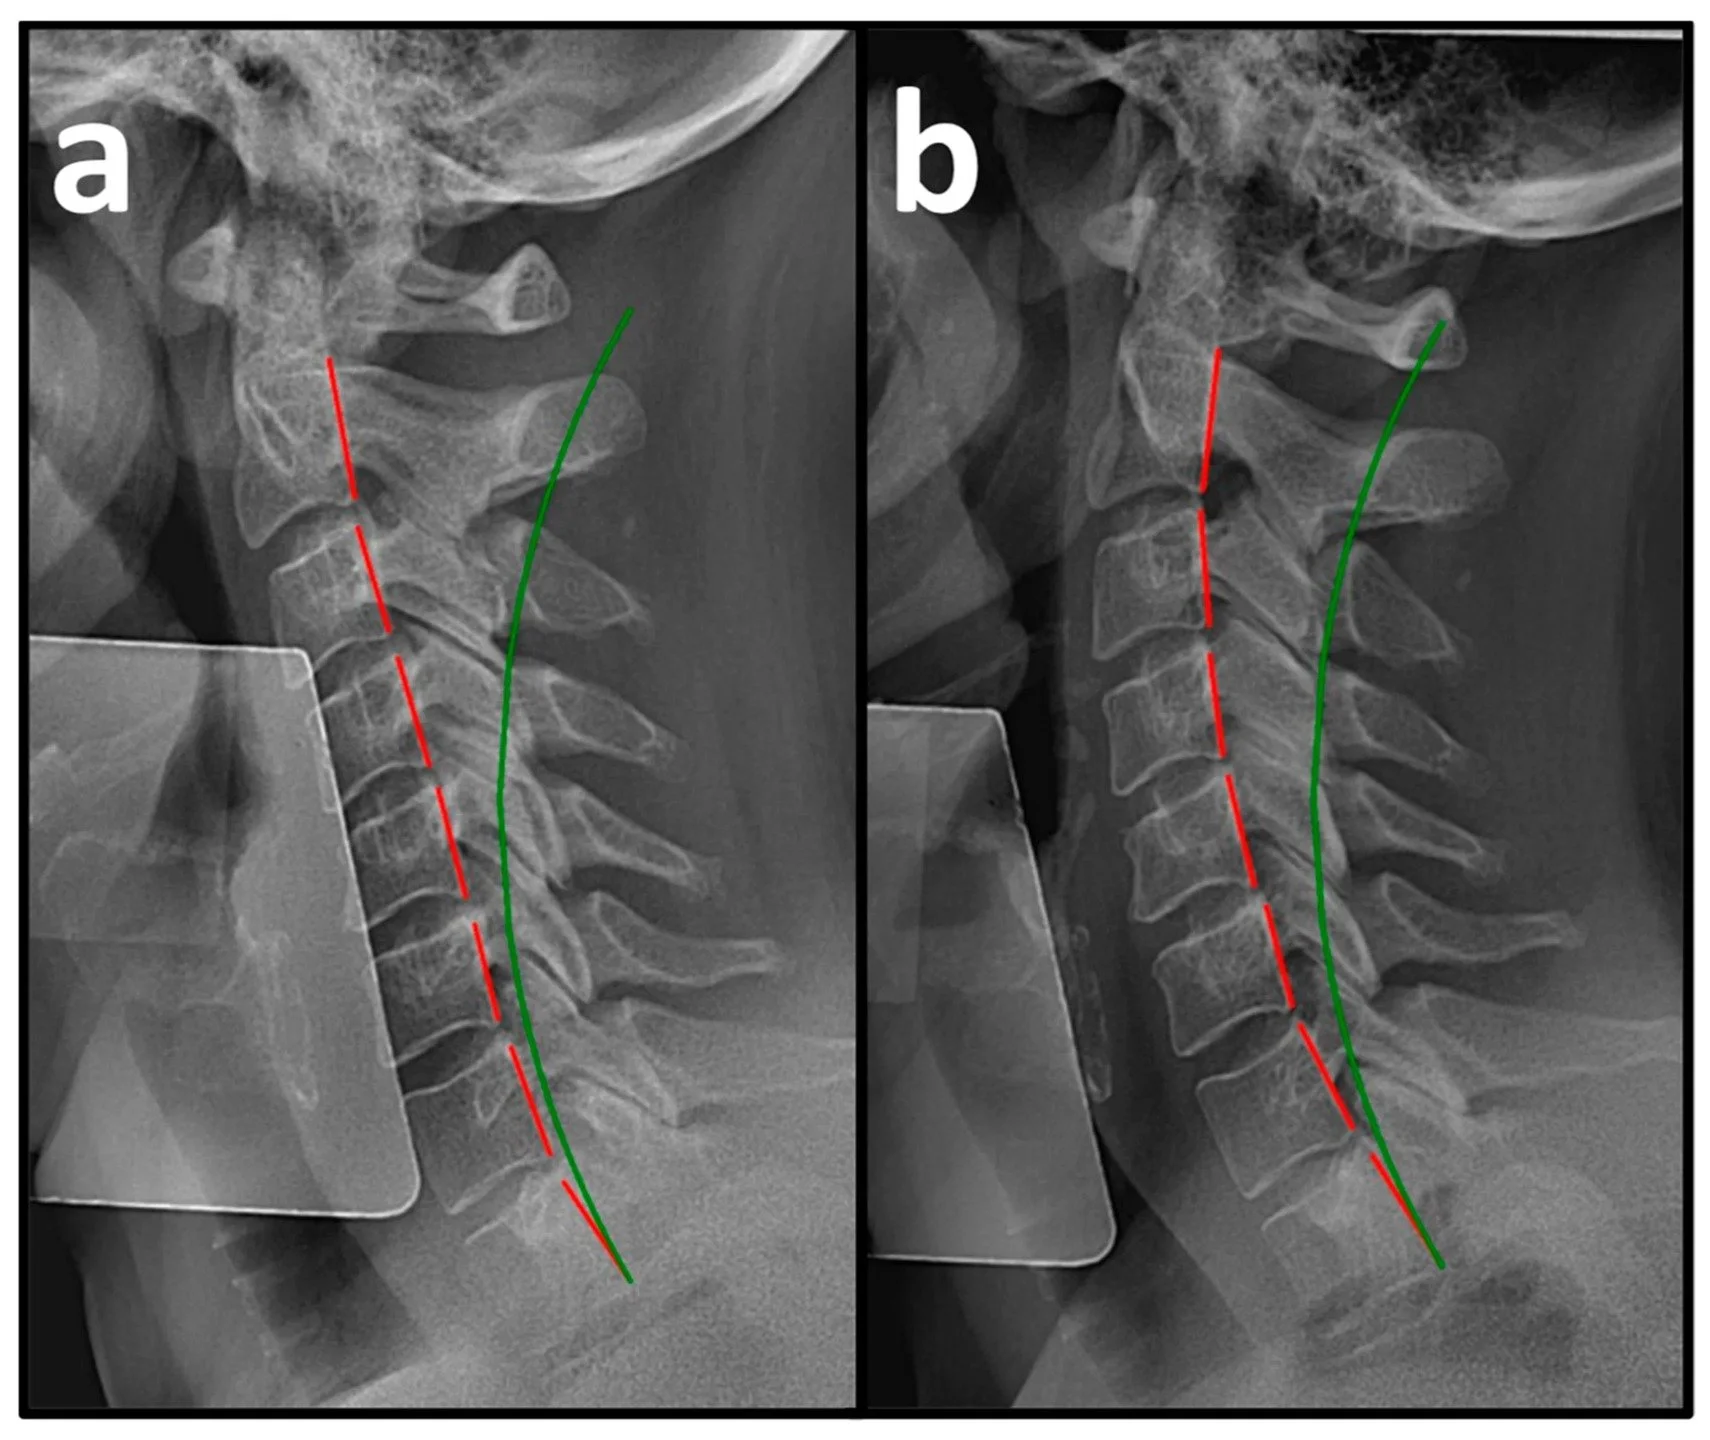

Precision Structural Correction:

Our Unique Approach to Spinal Health

At Structural Chiropractic, we don't just treat symptoms. We identify and correct the Structural Abnormalities that cause them.

We focus on Precision Structural Correction (PSC) – detecting and correcting the structural shifts in your spine that create problems throughout your body.

Structure Dictates Function

When a house's foundation moves out of proper position, the consequences throughout the structure can be severe. Wall fractures, squeaking floors, and stuck windows are merely signs pointing to the real problem: the foundation has shifted from where it should be.

Your spine works much the same way. When spinal alignment is compromised, it can trigger numerous health issues throughout your body. Treating only the symptoms without addressing Structural Abnormalities won't resolve the root problem and could allow progressive deterioration of your spine over time.